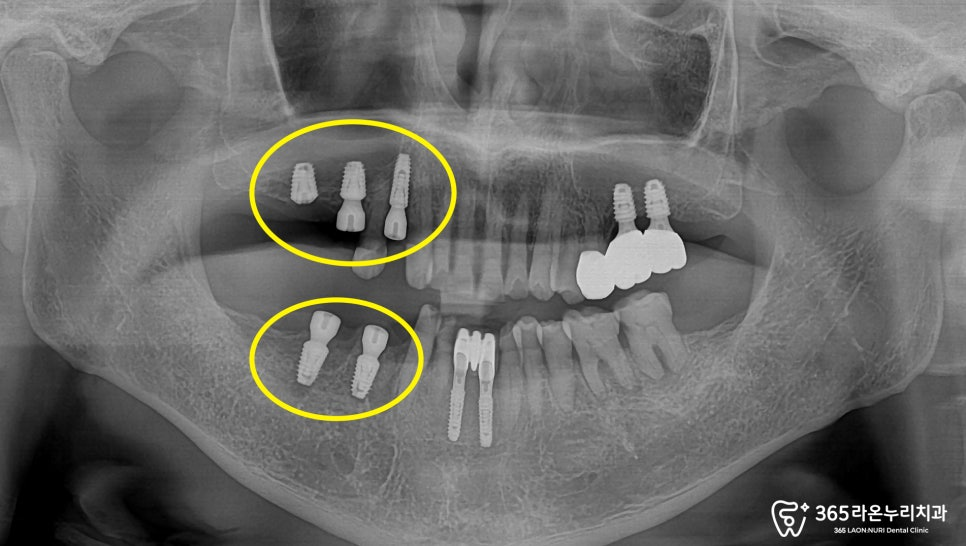

우선 눈에 띄는 아래 앞니부위부터

임플란트 식립을 진행해드렸습니다.

계획된 위치에 잘 심은 모습이

관찰되고 있습니다.

아래턱에 치료가 차례대로 진행되고 있는 모습이네요.

왼쪽 위턱의 뼈 양을 확인하고,

상악동 거상술로 임플란트 픽스처가

들어갈 공간 확보 및 뼈이식 과정을 함께

진행해드렸습니다!

임플란트 픽스처가 계획된

자리에 안정적으로 심어진 모습이

오른쪽 위 아래 턱 동그라미 친 부위에

심으면서 뼈이식을 함께 진행하려는

계획에 대해, 환자께 자세히

설명을 드렸던 흔적입니다. ^^

그리고, 오른쪽을 보시면 흔들리던

어금니가 사라지고 임플란트

수술을 통해 새로운

픽스처가 자리를 잡았습니다.

픽스처가 흔들리지 않게,

뼈이식 과정을 통해

튼튼하게 고정될 수 있게끔

만들어드렸습니다.